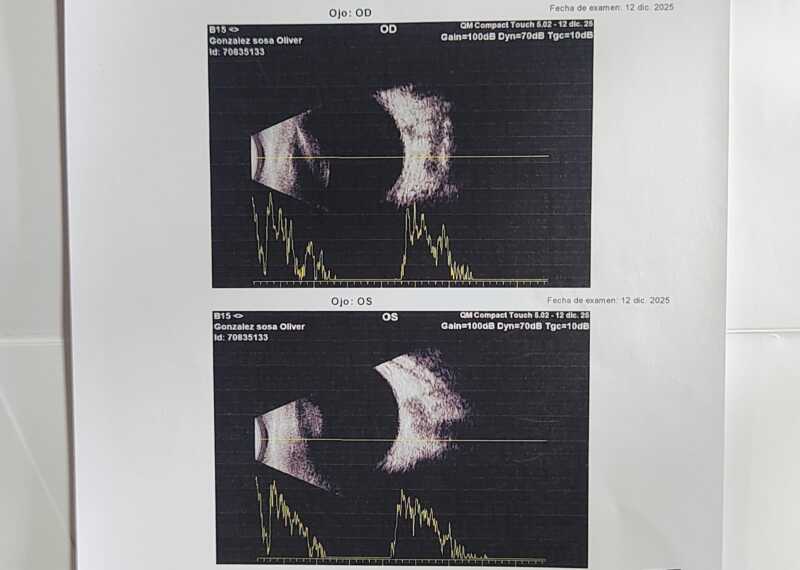

La historia moviliza por estas horas a vecinos y usuarios de redes sociales. Oliver nació con síndrome de Down y, tras una serie de estudios, los médicos confirmaron que presenta cataratas congénitas en ambos ojos. Según explicaron los especialistas, la cirugía no puede postergarse, ya que una demora podría generar consecuencias irreversibles en su capacidad visual y en su desarrollo neurológico.

Ante ese panorama, lograron contactar a un especialista que realiza cirugías oftalmológicas en bebés en el Sanatorio Borati, en Posadas. Allí completaron todos los estudios prequirúrgicos y recibieron el aval médico para avanzar con la operación, que fue programada para el jueves 15 de enero. Sin embargo, el costo total del procedimiento asciende a 20 millones de pesos, una cifra que la familia no puede afrontar por sus propios medios.